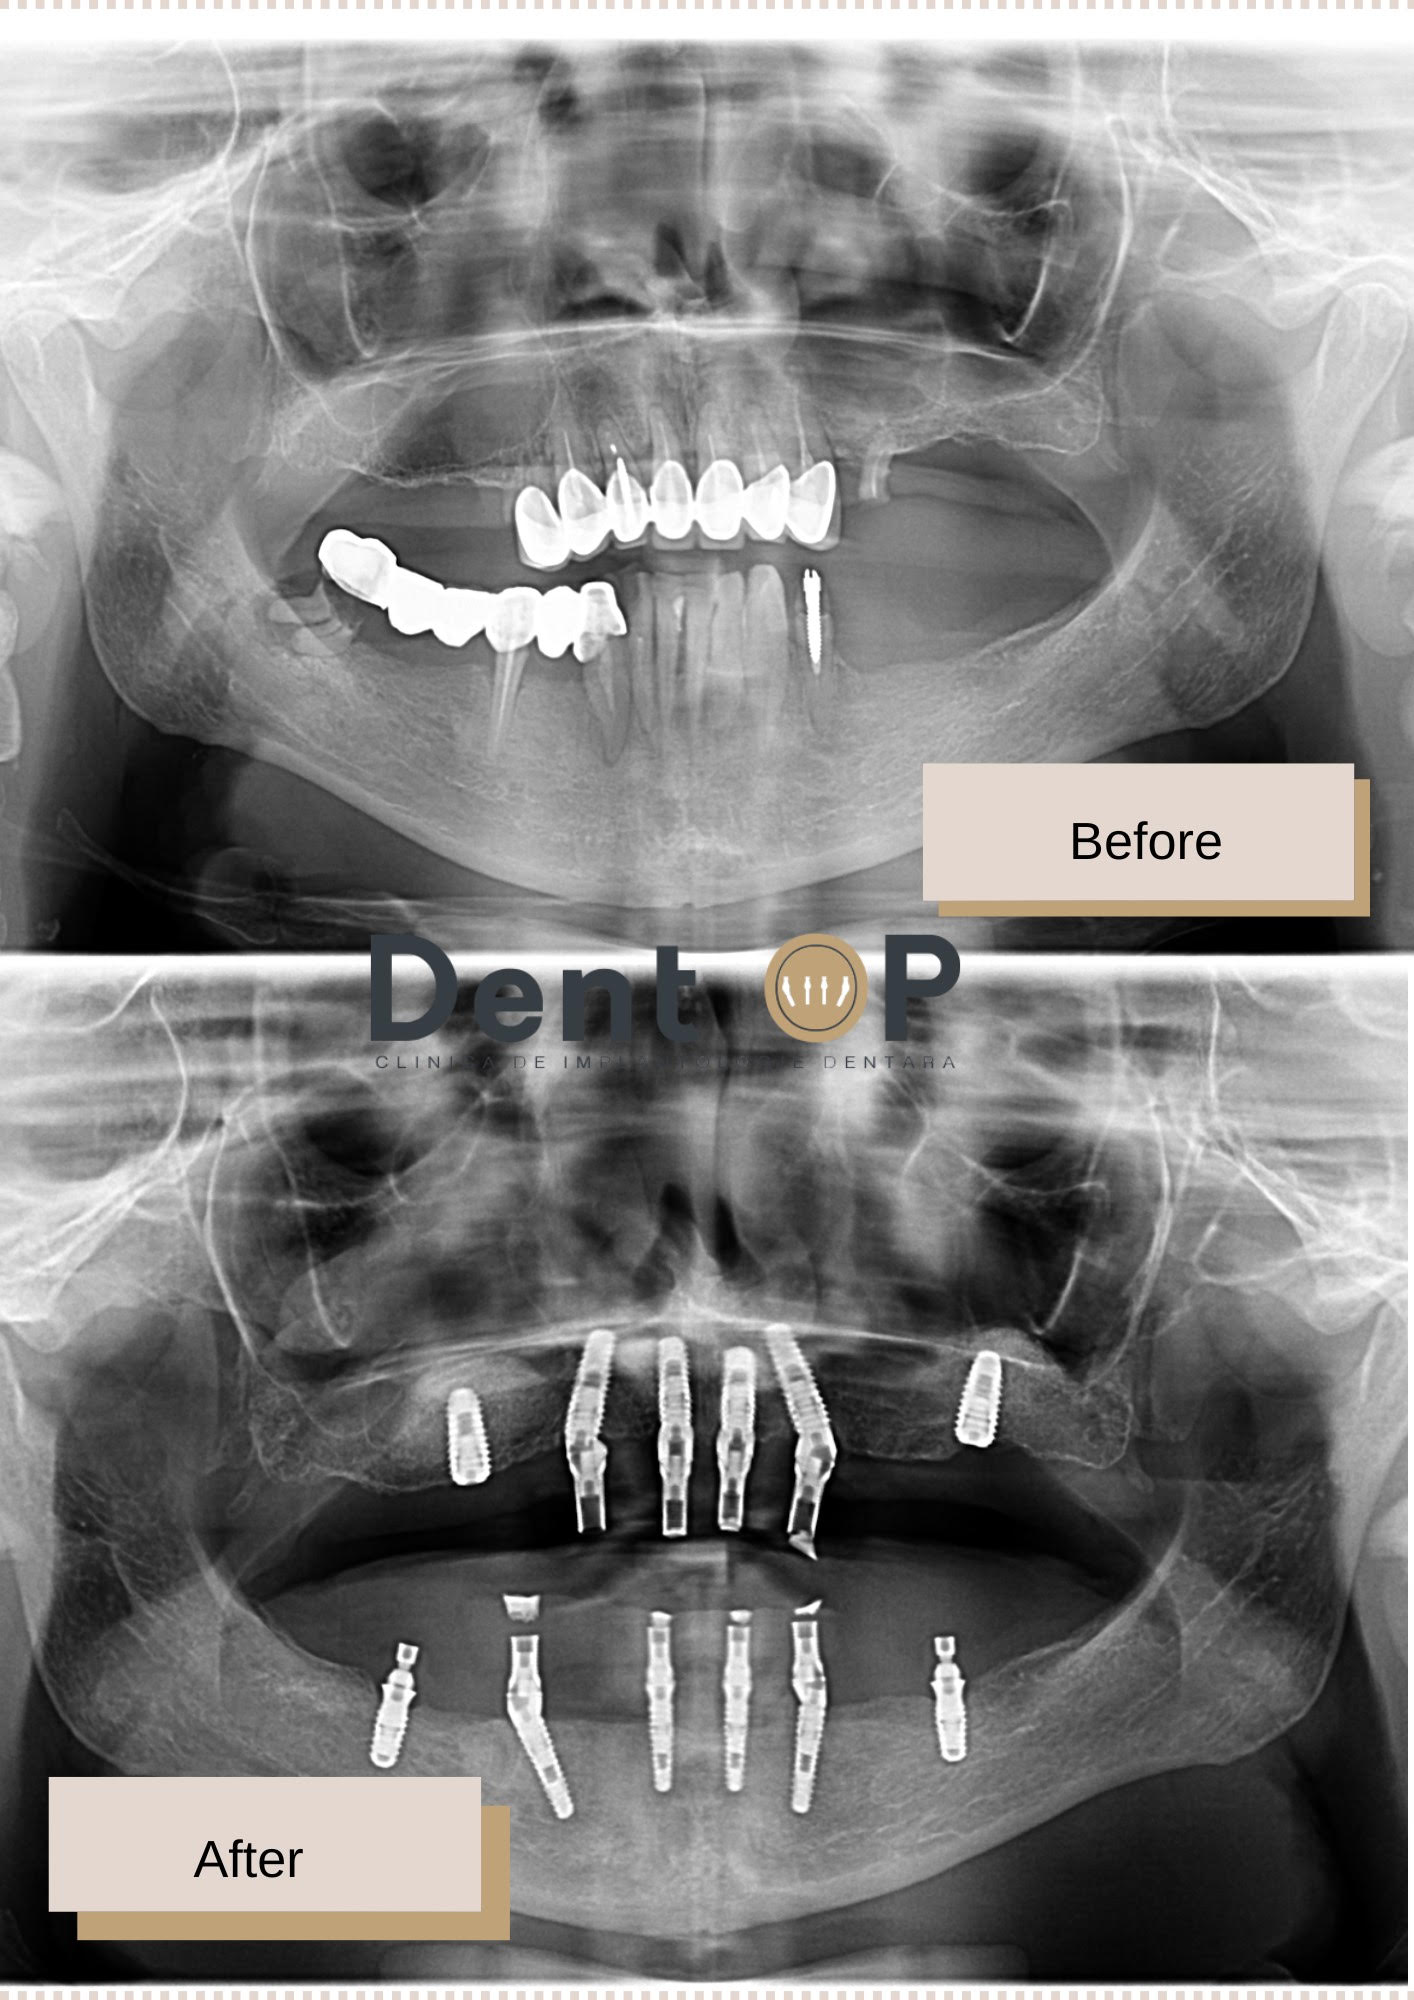

Dr Cazacu Corrado – Medic Specialist Chirurgie Dento-Alveolară a evaluat cu atenție starea dinților săi și i-a propus inserarea a 12 implanturi dentare (6 la maxilar și 6 la mandibulă) pe care s-a fixat o lucrare provizorie chiar din a doua zi.

Deja era foarte mulțumită după etapa lucrării provizorie, dar acum la 6 luni i-a fost inserată dantura finală pe care o va purta definitiv.